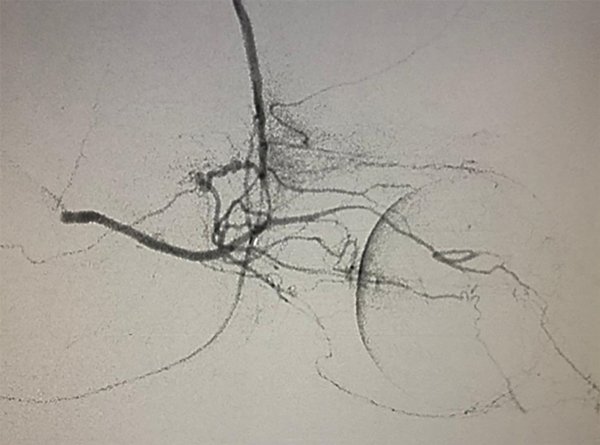

Puede presentarse la situación de observar escaso reflujo hacia la arteria carótida interna durante la adquisición superselectiva, esto no disminuye la efectividad siempre y cuando se logre una correcta opacificación de la coroides y se inyecten las drogas de manera pulsada y suave, según lo descripto por Jabbour et al. Si la maniobra no es satisfactoria se vuelve a repetir este paso. Si luego de dos (hasta tres) maniobras no se consigue cateterizar la arteria oftálmica se asume que no tiene un ostium “favorable” por lo que se da lugar a la siguiente fase de la técnica. Se posiciona el microcatéter en la arteria carótida externa y se cateteriza super-selectivamente la arteria meníngea media (o meníngea accesoria) para visualizar la anastomosis con arteria oftálmica (técnica 2 en 2 completa, fig. 5 y 6).

Fig 6: Cateterización superselectiva de arteria meníngea media (AMM) izquierda bajo road-mapping. Técnica “en dos pasos” o técnica “2 en 2 completa”. Vista lateral estricta. Microcatéter Marathon 1.5.